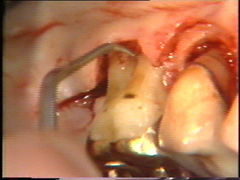

Observese como se

ha eliminado el tejido de granulación en el segundo premolar. |

Eliminación del

tejido de granulación |